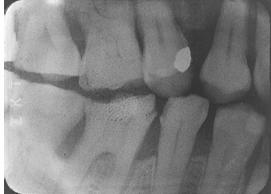

What is the problem with this Overexposed Receptor X-ray?

May occur with digital sensors or film, Excessive exposure time, kilovoltage, or milliamperage, Image appears dark or High density

How would you resolve this Overexposed Receptor X-ray?

Check settings and reduce as needed prior to exposing receptor